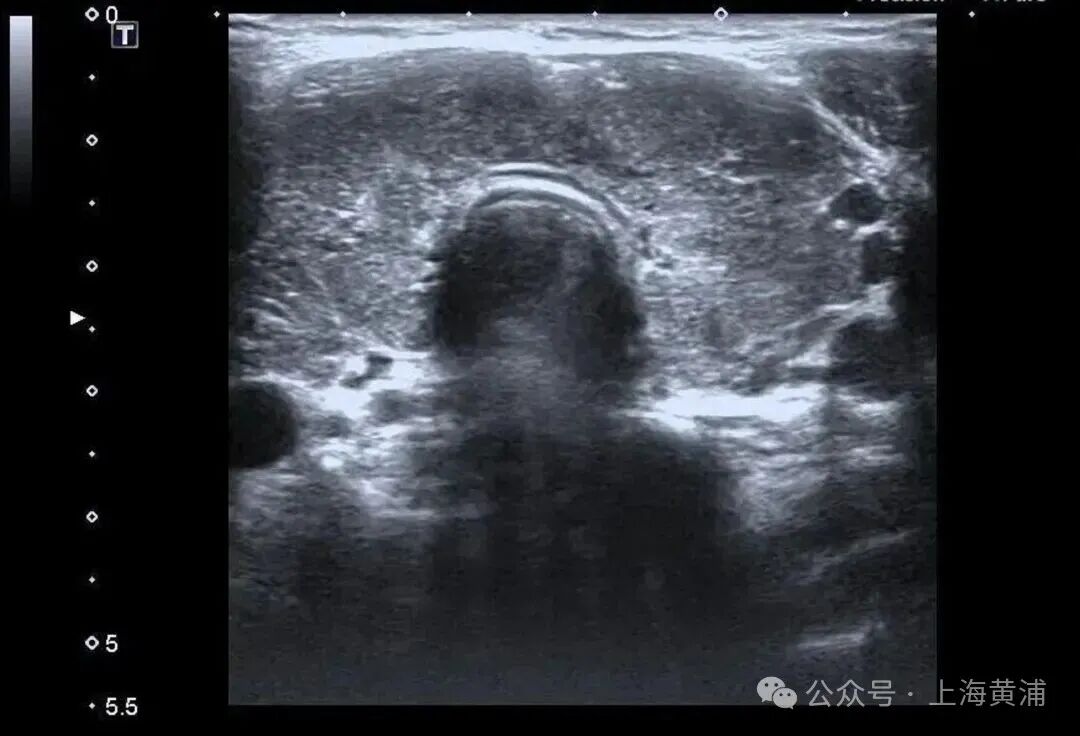

入院后的检查结果显示

陈女士的身体

正被一场“激素风暴”席卷

甲状腺功能检查中,游离T3高达20.83 pmol/L(正常值3.5 - 6.5pmol/L),游离T4高达88.42 pmol/L(正常值11.5 - 22.7pmol/L),这两项核心激素都超过正常上限数倍,而本应调控它们的促甲状腺激素(TSH)却几乎测不出来,这明确证实了陈女士患有极其严重的甲状腺毒症。心脏超声结果同样不容乐观,射血分数仅有40%(正常应高于55%),这意味着心脏泵血能力大幅下降。

同时,CT检查发现她的双侧胸腔、腹腔存在积液。综合各项检查结果,医生判断陈女士患上了甲状腺危象,这是甲亢最凶险的并发症。